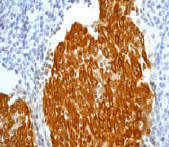

Anti-Cytokeratin 5 antibody [EPR1600Y](ab75869)

Rabbit Recombinant Monoclonal Cytokeratin 5 antibody. Suitable for IHC-P, WB, ICC/IF, Flow Cyt (Intra) and reacts with Human samples. Cited in 27 publications.

Applications Flow Cyt (Intra), ICC/IF, IHC-P, IP, WB

Species Reactivity Human